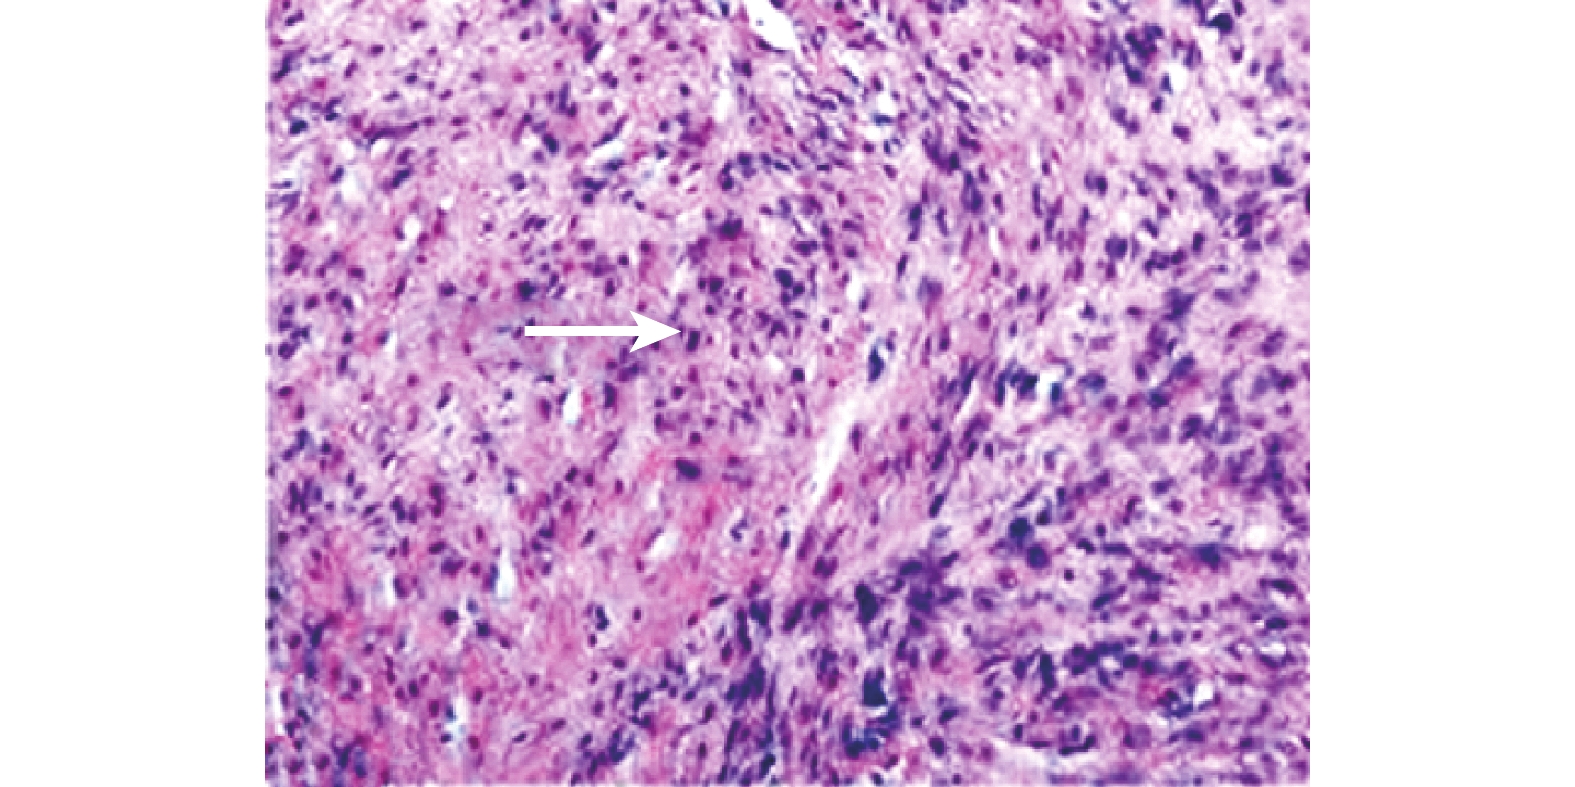

圖3

術后病理學檢查示瘤細胞呈梭形,束狀排列(白箭), 呈侵襲性生長(HE ×100)

本組病例中有 7 例在術前未行病理學診斷,1 例外院術后復發患者于外院行病理學檢查確診為 AF。8 例患者的切除標本術后送病理學檢查:腫物切開時有沙礫感,切面白色有光澤(圖 2);腫物直徑為 3.5~12.5 cm,平均 7.1 cm。全部患者術后均經病理學檢查診斷為 AF,HE 染色后鏡下見腫瘤細胞以梭形為主,束狀排列,呈侵襲性生長(圖 3);鏡下細胞以一致性長形、梭形細胞增生為主,周圍可見膠原性間質和數量不等的血管,血管可見部分水腫。